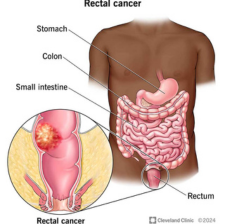

Anal / Colon / Rectal Cancer

Colon cancer is a cancer that forms in the tissues of the colon (the longest part of the large intestine). Rectal cancer is a cancer that forms in the tissues of the rectum (the last several inches of the large intestine closes to the anus. Colorectal cancer affects the digestive system.